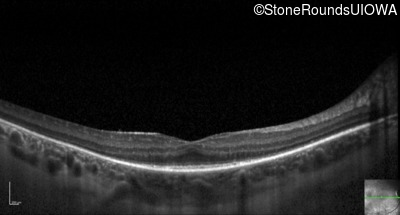

Optical Coherence Tomography - Left - 20/32 -1

Exemplar / OCT Stack

OCT Stack